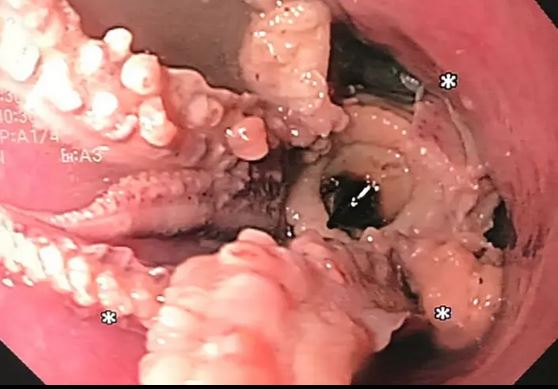

Οι γιατροί που τον εξέτασαν έμειναν άναυδοι όταν ανακάλυψαν ότι οι ενοχλήσεις στο λαιμό του άνδρα οφείλονταν σε ένα χταπόδι που είχε κολλήσει στο φάρυγγά του.

Οι γιατροί πραγματοποίησαν αξονική τομογραφία, η οποία αποκάλυψε μια υπερπυκνή μάζα στον οισοφάγο του άνδρα.

Μια επακόλουθη εξέταση έδειξε ένα χταπόδι ζωντανό με πλοκάμια να έχει σφηνωθεί δύο εκατοστά από τα όρια οισοφάγου-στομάχου. Οι γιατροί αφαίρεσαν το χταπόδι με λαβίδα.